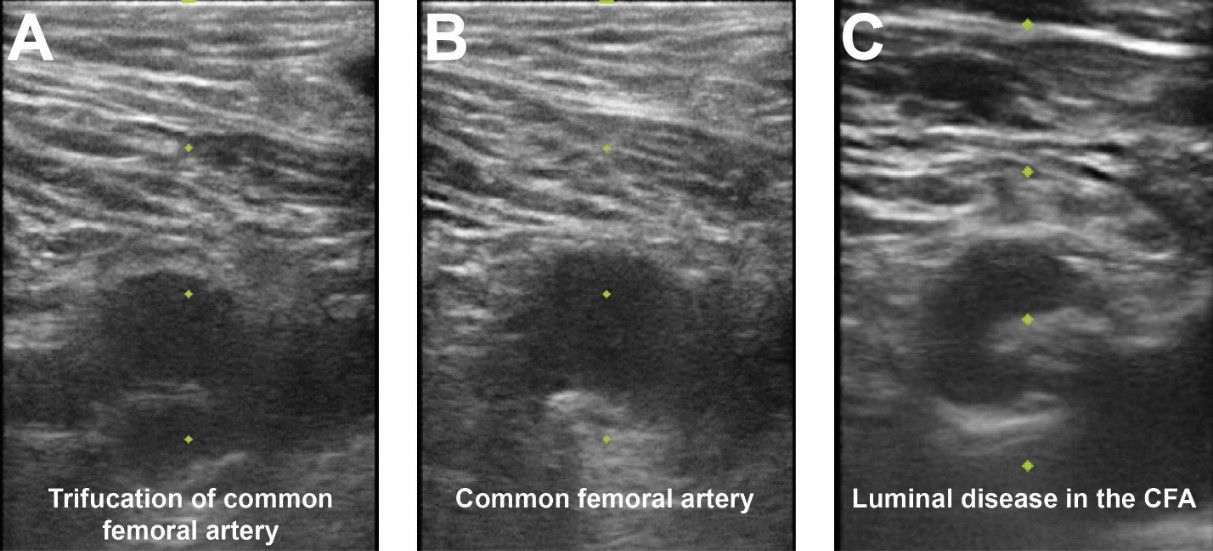

Contemporary femoral access should utilize all available techniques and adjunctive information available to reproducibly achieve vascular access with the lowest complication rate possible [18]. With the patient supine on the catheterization table, anatomic landmarks should be assessed. In patients with a large body mass index, retraction of the pannus can facilitate vascular access as well as hemostasis and closure. Placement of a radiopaque marker (hemostat) should be utilized in conjunction with fluoroscopy to assess the lower edge of the femoral head (Fig. 2). This location can be marked with a sterile pen and may help avoid high puncture. Ultrasound should then be performed to assess the ideal entry point for CFA access. The ultrasound probe can initially be placed perpendicular to the patient at the location of the lower edge of the femoral head as previously identified. Prior to attempting access the operator should assess the femoral artery anatomy including the location of the CFA bifurcation into SFA and PFA and evaluate for any major branch vessel, areas with severe calcification or obstructive peripheral arterial disease that should be avoided (Figs. 3,4). Longitudinal assessment of the CFA as it dives into the pelvis can also help the operator avoid high access, as well as visualization of the femoral head. Once the ideal target area of vascular access has been located with the ultrasound probe, careful attention should be given to any manipulation of the ultrasound probe. The ultrasound probe should be static and maintained straight without any tilting or angulation. Skin puncture with the access needle should occur 1–2 cm distal to the probe while aligned with the center marker on the probe and approximately 30–45 degrees. Steep angulations should be avoided as they can contribute to sheath or wire kinking. Following needle entry into the CFA, a J-tipped or micropuncture wire is introduced. Routine fluoroscopic assessment of needle entry location with the J-tipped/micropuncture wire in place (Fig. 2) should be performed to confirm that the needle entry is over the femoral head. If the needle entry is below or above the femoral head, this safety step allows for removal of the needle to reattempt access. If the needle entry site is satisfactory, then the wire can be advanced, however, tracking of the access wire should be pursued fluoroscopically when using the micropuncture wire as it can enter side-branches such as the inferior epigastric or deep circumflex iliac branches and cause perforations [28]. Following sheath insertion, femoral artery angiography [usually 30 degrees right anterior oblique (RAO) for right CFA access and 30 degrees for left CFA access] should be obtained to confirm safe access without complications, as well as help evaluate the anatomy and assess for tortuosity or peripheral arterial disease (Fig. 2). Occasionally additional angiographic projections may be required to confirm entry site. While femoral angiography can be performed through the micropuncture sheath, the latter provides limited opacification and has the risk for complications such as vessel dissection given that the injection is performed without assessment of hemodynamic waveform and the microcatheter sheath may be positioned against the vessel wall. Therefore, our suggested approach is that femoral angiography should preferably occur with the J-wire in place as such deflects the sheath from the vessel wall and maintains vessel control should complications occur. C-arm rotation can also be utilized to facilitate needle entry visualization. A standard setup for contemporary femoral access is shown in Fig. 5.

Fig. 3.Femoral access ultrasound. (A) Femoral artery ultrasound shows a trifurcation of the CFA and femoral vein to image right. (B) Superior to the CFA bifurcation is seen in an area amenable for vascular access. (C) CFA ultrasound noting significant luminal atherescolosis.